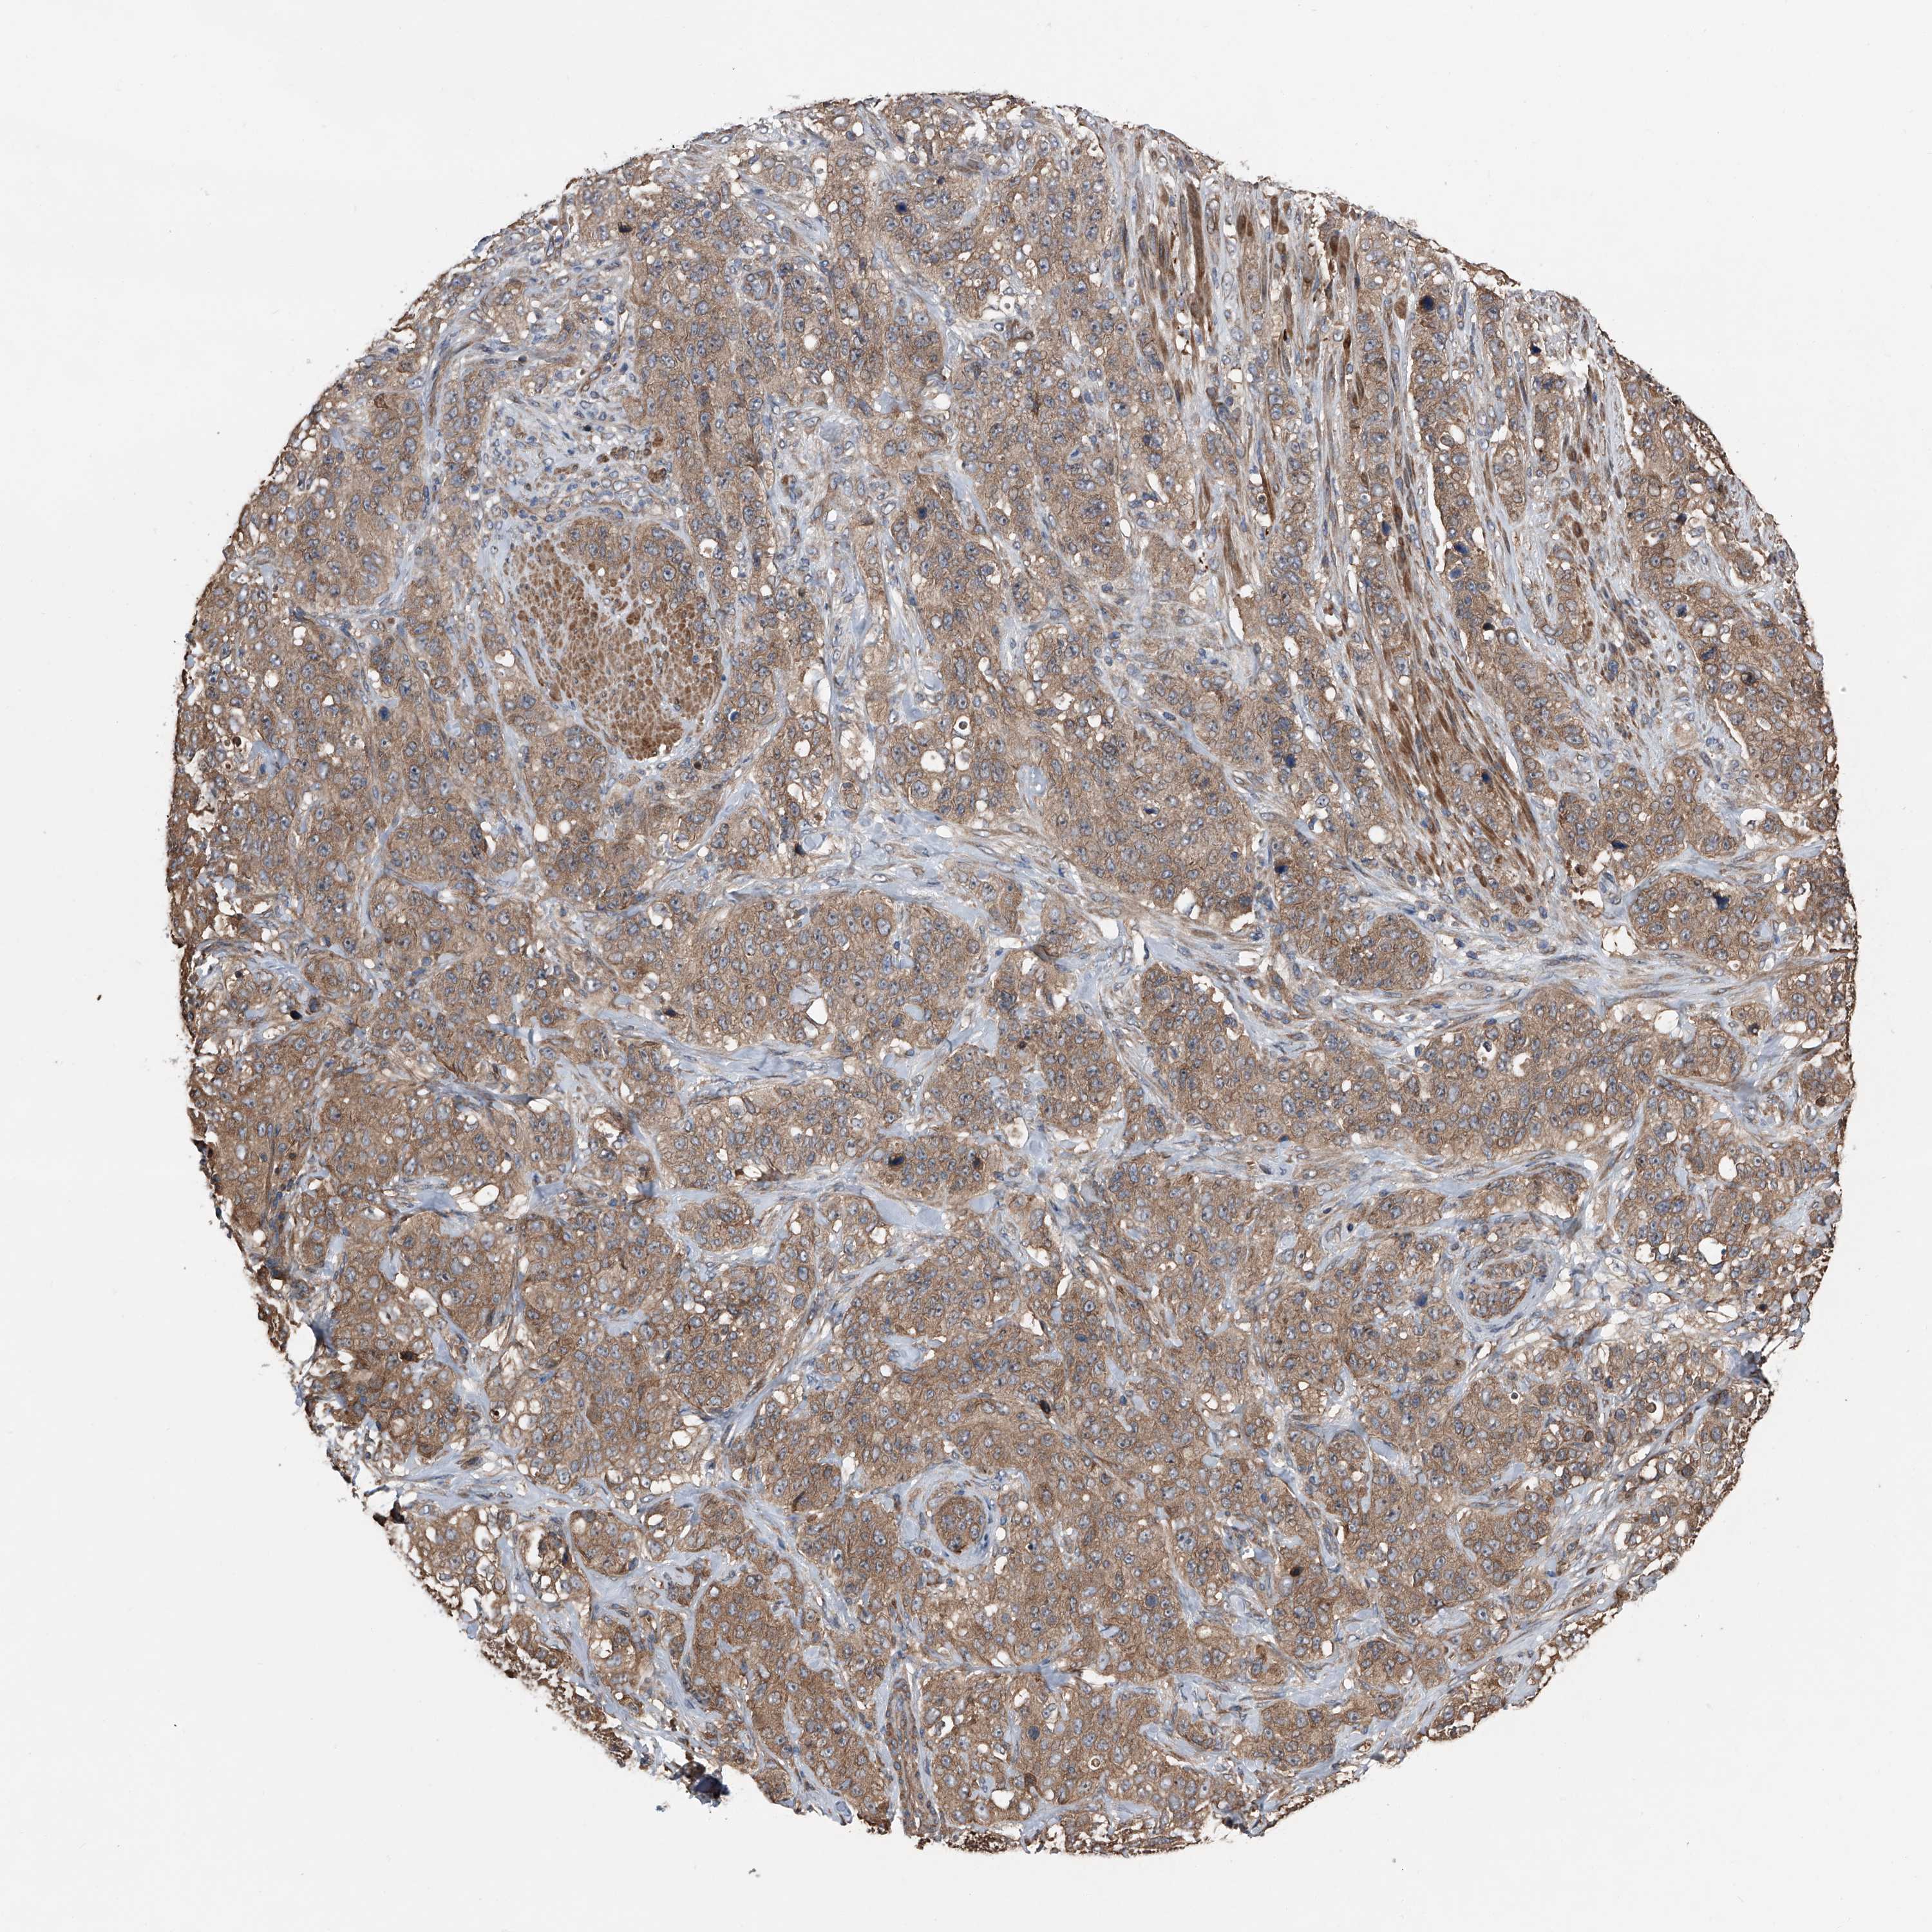

STOMACH CANCER - Protein expressioni

A mouse-over function shows sample information and annotation data. Click on an image to view it in a full screen mode. Samples can be filtered based on level of antibody staining by selecting one or several of the following categories: high, medium, low and not detected. The assay and annotation is described here.

Note that samples used for immunohistochemistry by the Human Protein Atlas do not correspond to samples in the TCGA dataset.

Antibody stainingi

Antibody staining in the annotated cell types in the current human tissue is reported as not detected, low, medium, or high, based on conventional immunohistochemistry profiling in selected tissues. This score is based on the combination of the staining intensity and fraction of stained cells.

Each image is clickable and will lead to virtual microscopy that enables deeper exploration of all samples and also displays staining intensity scores, fraction scores and subcellular localization as well as patient and tissue information for each sample.

Antibody HPA029109

Staining

High

Medium

Low

Not detected

Intensity

Strong

Moderate

Weak

Negative

Quantity

>75%

75%-25%

<25%

None

Location

Nuclear

Cytoplasmic/membranous

Cytoplasmic/membranous,nuclear

Adenocarcinoma, NOS